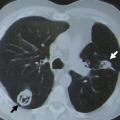

L’atteinte pulmonaire est variable : infiltrats alvéolaires, aspect en verre dépoli, nodules multiples excavés (fig. 9). L’hémorragie alvéolaire, complication majeure mais rare de la granulomatose avec polyangéite, se produit au niveau de la circulation pulmonaire distale entraînant un comblement alvéolaire (fig. 10). Elle se manifeste par une hémoptysie, une dyspnée, une anémie, des opacités diffuses alvéolaires et un liquide hémorragique au lavage bronchoalvéolaire (LBA). Des sténoses trachéo­bronchiques sont possibles.